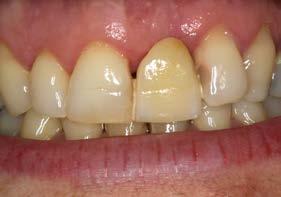

Tras 6 meses de oseointegración, se procedió a la confección de la prótesis definitiva. En aquel momento, hace 22 años, se eligió un biopilar microfresado y una corona metal-cerámica cementada, que representaban la mejor alternativa para garantizar un sellado adecuado y una estética satisfactoria en el sector anterior. En la actualidad, la opción preferible habría sido una prótesis atornillada con un elemento intermedio (transepitelial unitario) y una corona totalmente cerámica cementada a una interfase. No obstante, es importante contextualizar la decisión en función de la época en la que se finalizó el caso (Figuras 12 y 13).

La paciente ha permanecido en seguimiento y mantenimiento clínico durante 22 años, sin evidenciarse pérdidas óseas periimplantarias ni recesión gingival en torno al perfil de emergencia (Figura 14). En la actualidad, se realizó

Estos hallazgos confirman el éxito del procedimiento quirúrgico y de la posterior carga progresiva, con un mantenimiento óptimo de los tejidos duros y blandos a lo largo de más de dos décadas (Figura 15). Los cambios entre el momento inicial y el final del tratamiento son evidentes, especialmente al comparar la imagen intraoral de la primera visita con la tomada a los 22 años, donde la mucosa que rodea al diente 21 —y posteriormente al implante— se muestra engrosada, en buen estado de salud y con una estética destacable. Asimismo, la comparación entre la radiografía inicial, que evidenciaba el fracaso del tratamiento de conductos del diente en posición 21, y la radiografía a los 22 años, que muestra el implante sin pérdidas óseas asociadas, resulta elocuente (Figuras 16 a 19).